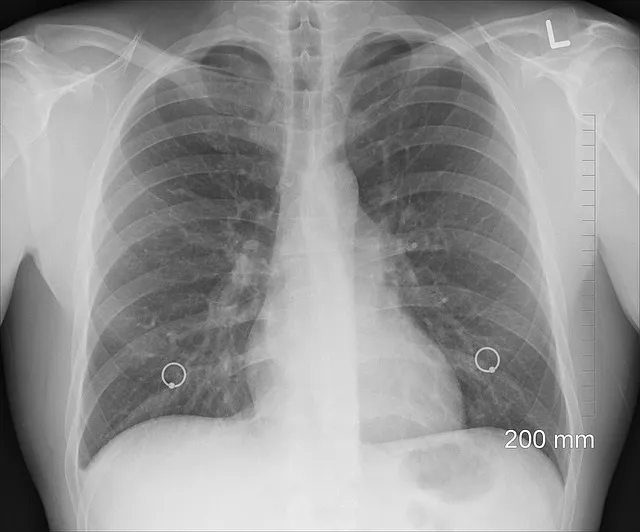

Jelentős a különbség az oltott és oltatlan betegek tüdőkárosodása tekintetében koronavírus-fertőzés esetén.

„A koronavírussal megfertőződött, de beoltott emberek több mint 95%-ának nem károsodik a tüdeje” – állítja a temesvári Victor Babeș Fertőző- és Pneumoftiziológiai Kórház orvos igazgatója, Diana Manolescu.

Állítását röntgenfelvételekkel támasztotta alá a szakember:

A koronavírussal kórházba került oltott és nem oltott személyek esetében a legnagyobb különbség a tüdő károsodásában vehető észre. Míg a beoltott emberek 95 százalékánál nincs tüdőkárosodás, addig az oltatlanok esetében a tüdő jelentősen károsodik.

„Az oltatlan betegeknél a tüdőkárosodás 30-40 százalékkal kezdődik, és rövid időn belül tovább romolhat, akár 70-80, sőt 85 százalékosra is” – mondta Diana Manolescu. „Sajnos ezek a tüdőelváltozások gyakran összeegyeztethetetlenek az élettel” – magyarázta. „Az egyetlen megoldás a védőoltás” – zárta a videót a doktornő.